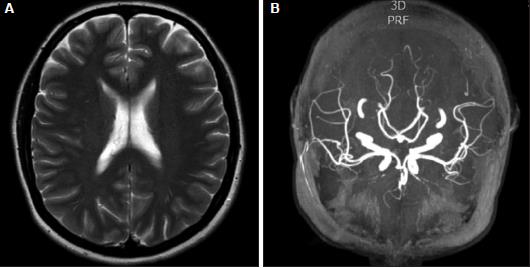

In 1988 Gregory Call and Marie Fleming described a unique clinical and radiographic syndrome in a small case series of 4 patients presenting with acute headache and reversible cerebral artery vasoconstriction. In the cases described here CFS was associated with subarachnoid haemorrhage. Calcium channel blockers nimodipine for vasospasm Syndrome is benign with excellent 95 recovery Day 2 MRIMRA Day 2.

The Call-Fleming syndrome CFS comprises acute severe recurrent thunderclap headaches occasional transient or fluctuating neurological abnormalities and reversible segmental. Reversible cerebral vasoconstriction syndrome is an increasingly recognized headache disorder characterized by recurring severe sudden-onset headaches that may be accompanied by focal neurological deficits.